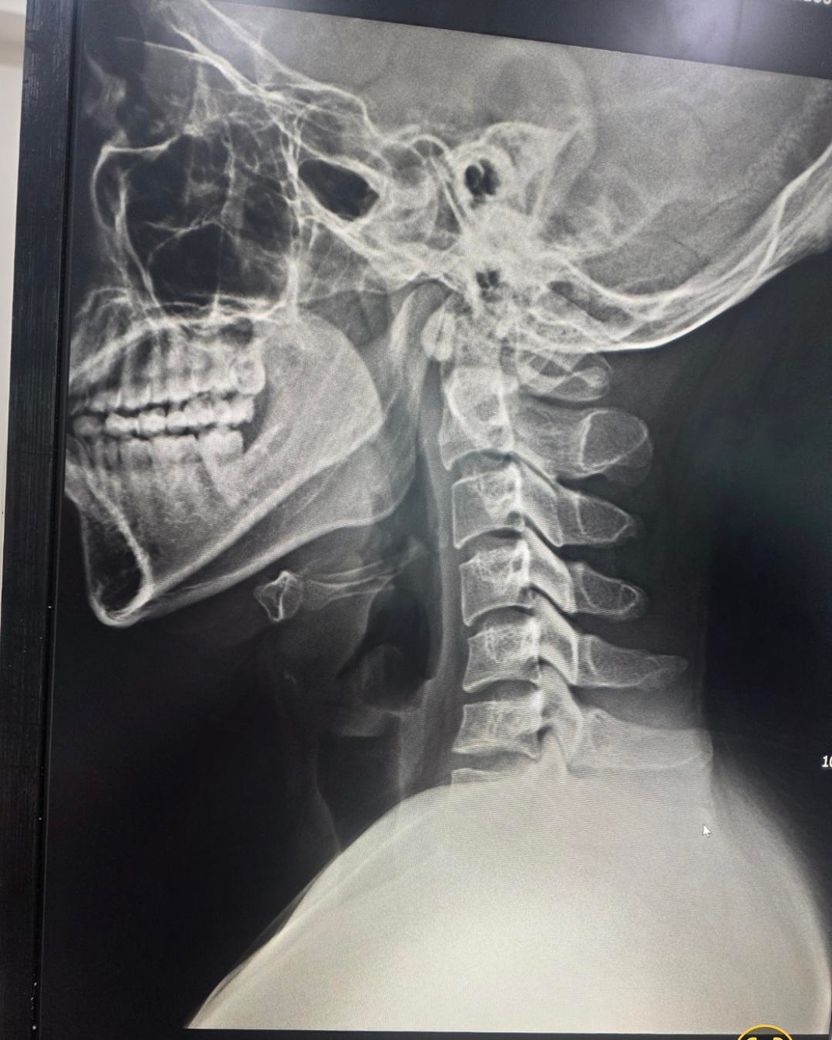

• 제시된 측면 X-ray와 시상면 MRI를 기준으로 보면, 경추 전만이 감소한 이른바 거북목 형태가 뚜렷하고, 하부 경추에서 디스크의 퇴행성 변화와 경미한 후방 돌출이 의심됩니다. MRI에서 척수는 연속성은 유지되며 뚜렷한 압박이나 신호 변화는 뚜렷하지 않아, 현재 단계는 “경추 정렬 이상 + 초기 디스크 퇴행/팽윤” 범주로 해석하는 것이 타당합니다. 즉 구조적 파열이나 심한 협착보다는, 자세와 근육 불균형에 의해 반복적으로 증상이 재발하는 상태에 가깝습니다.